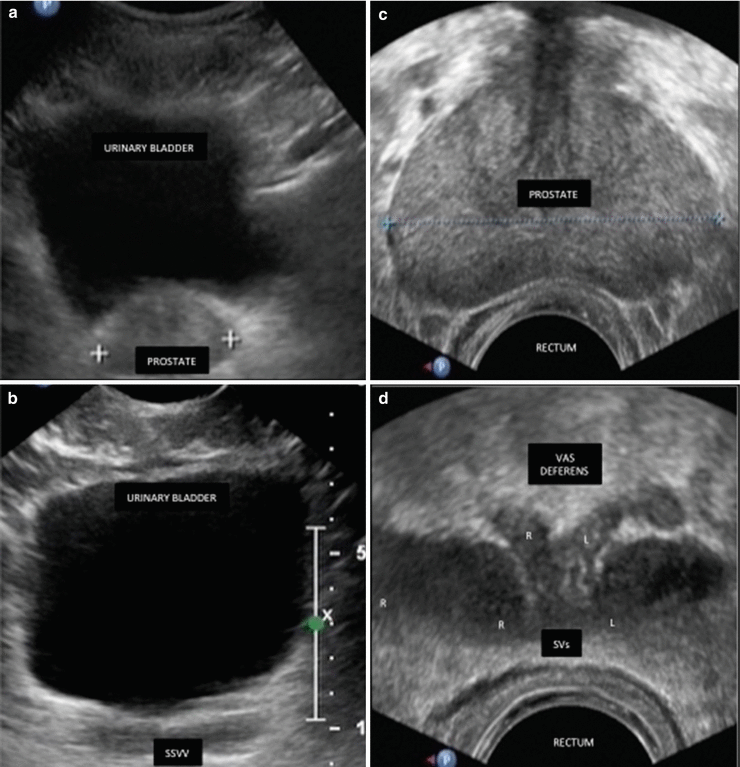

Fig. 9.3

Anatomy of the prostate, seminal vesicles, and vas deferens. (a,b) Abdominal US. (c,d) Transrectal US. Seminal vesicles (SVs) are two homogeneous, hypoechoic ovals that extend laterally upward from the bladder. Prostate is an elliptical, chestnut-shaped gland with smooth margins and a homogeneous internal echo pattern. The distal portion of the vas deferens is seen as a slightly dilated tubular structure (ampulla) medial to the SVs